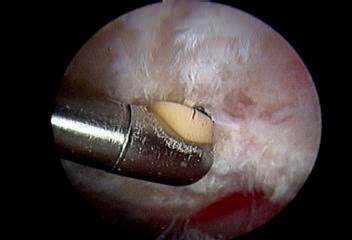

1.肩峰下间隙清理

这一方法适用于年龄较大,运动要求不高的人群。医生在手术中仅仅对肩峰下间隙进行清理同时对肩峰进行成形。

肩关节镜下炎性、增生组织清理